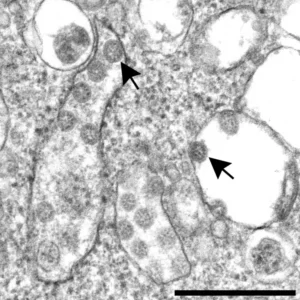

While viruses were discovered only decades after Koch, cannot be cultured in the classic sense, and cannot be seen with a conventional light microscope, they are still very real.